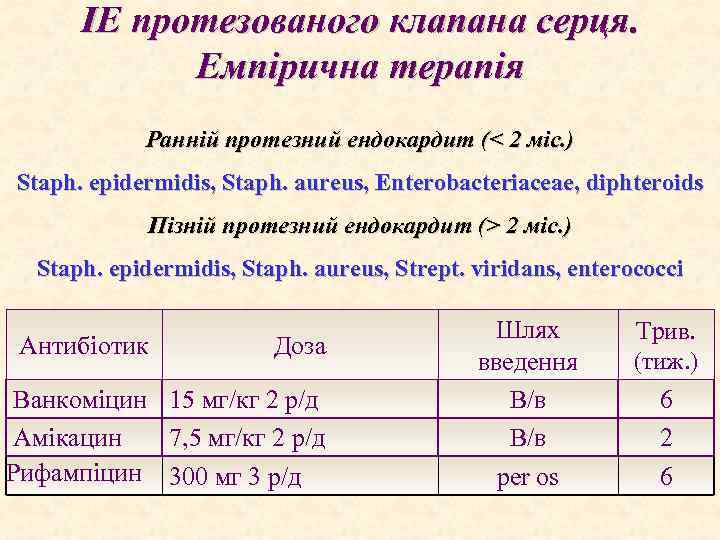

ІЕ протезованого клапана серця. Емпірична терапія Ранній протезний ендокардит (< 2 міс. ) Staph. epidermidis, Staph. aureus, Enterobacteriaceae, diphteroids Пізній протезний ендокардит (> 2 міс. ) Staph. epidermidis, Staph. aureus, Strept. viridans, enterococci Антибіотик Доза Ванкоміцин 15 мг/кг 2 р/д Амікацин 7, 5 мг/кг 2 р/д Рифампіцин 300 мг 3 р/д Шлях введення В/в per os Трив. (тиж. ) 6 2 6